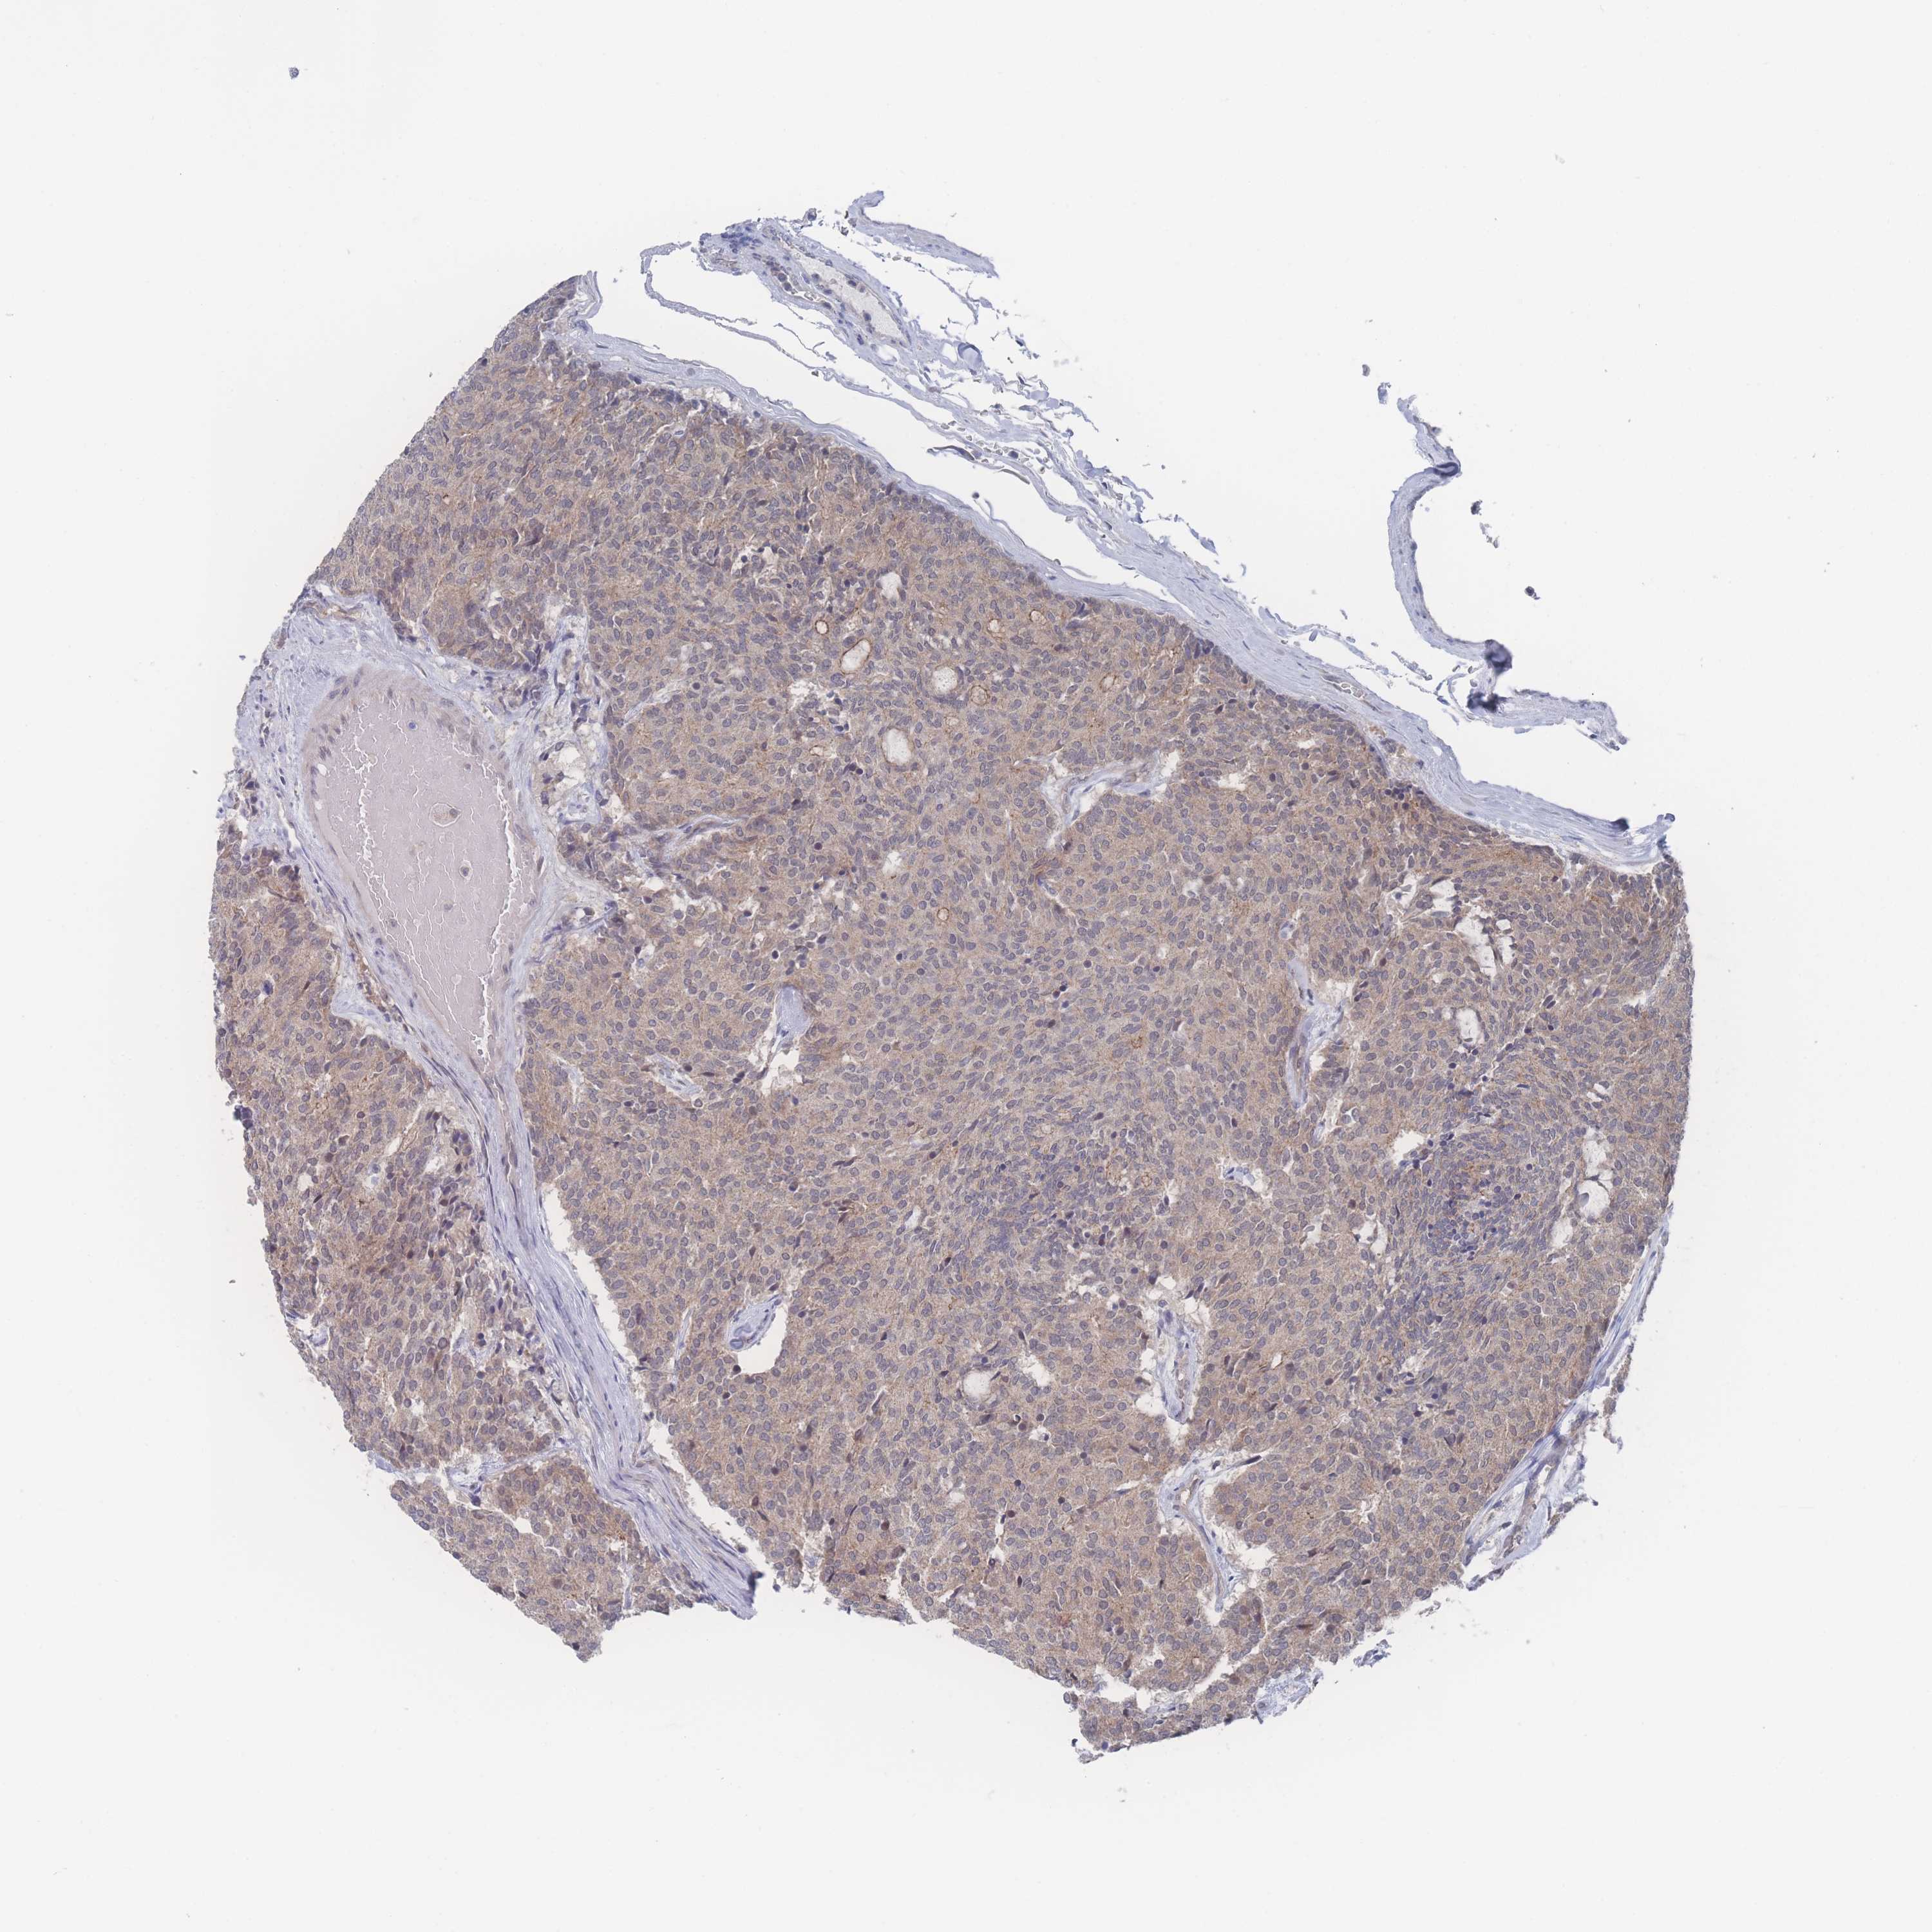

CARCINOID - Protein expressioni

A mouse-over function shows sample information and annotation data. Click on an image to view it in a full screen mode. Samples can be filtered based on level of antibody staining by selecting one or several of the following categories: high, medium, low and not detected. The assay and annotation is described here.

Antibody stainingi

Antibody staining in the annotated cell types in the current human tissue is reported as not detected, low, medium, or high, based on conventional immunohistochemistry profiling in selected tissues. This score is based on the combination of the staining intensity and fraction of stained cells.

Each image is clickable and will lead to virtual microscopy that enables deeper exploration of all samples and also displays staining intensity scores, fraction scores and subcellular localization as well as patient and tissue information for each sample.

Antibody HPA049189

Staining

High

Intensity

Strong

Quantity

>75%

Location

Nuclear

Carcinoid, malignant, NOS